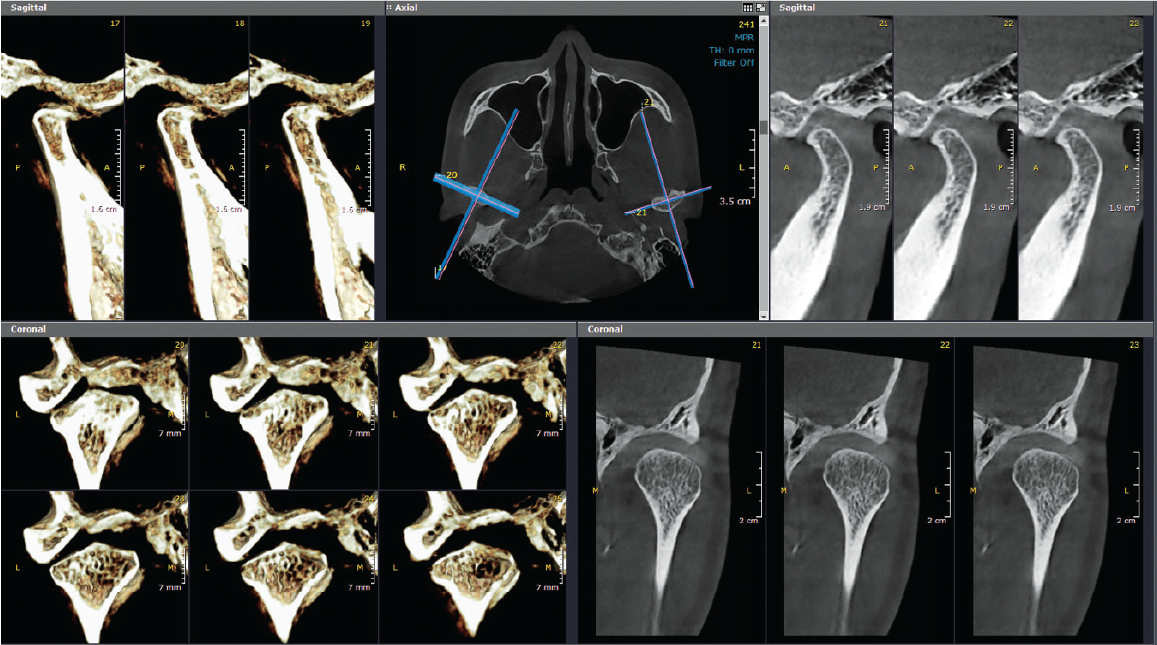

The Dentri MAX is the flagship model from HDX WILL, with the largest avail max FOV at 18x16.5, suitable for a wide scope of uses including advanced implantology, endodontics, orthodontics, orthognathic, bilateral TMJ & airway studies.

Adaptive Exposure Control reduces radiation emission corresponding to the thickness of the object up to 50%. Precision MAR (Metal Artifact Reduction) algorithm ensures the clearest diagnostic images even in presence of metallic objects.

Fully spec'd 3D software suite including all the above study/analysis modules, with zero subscription fees and unlimited 1-on-1 expert training so you can get the most out of this premium tier machine.